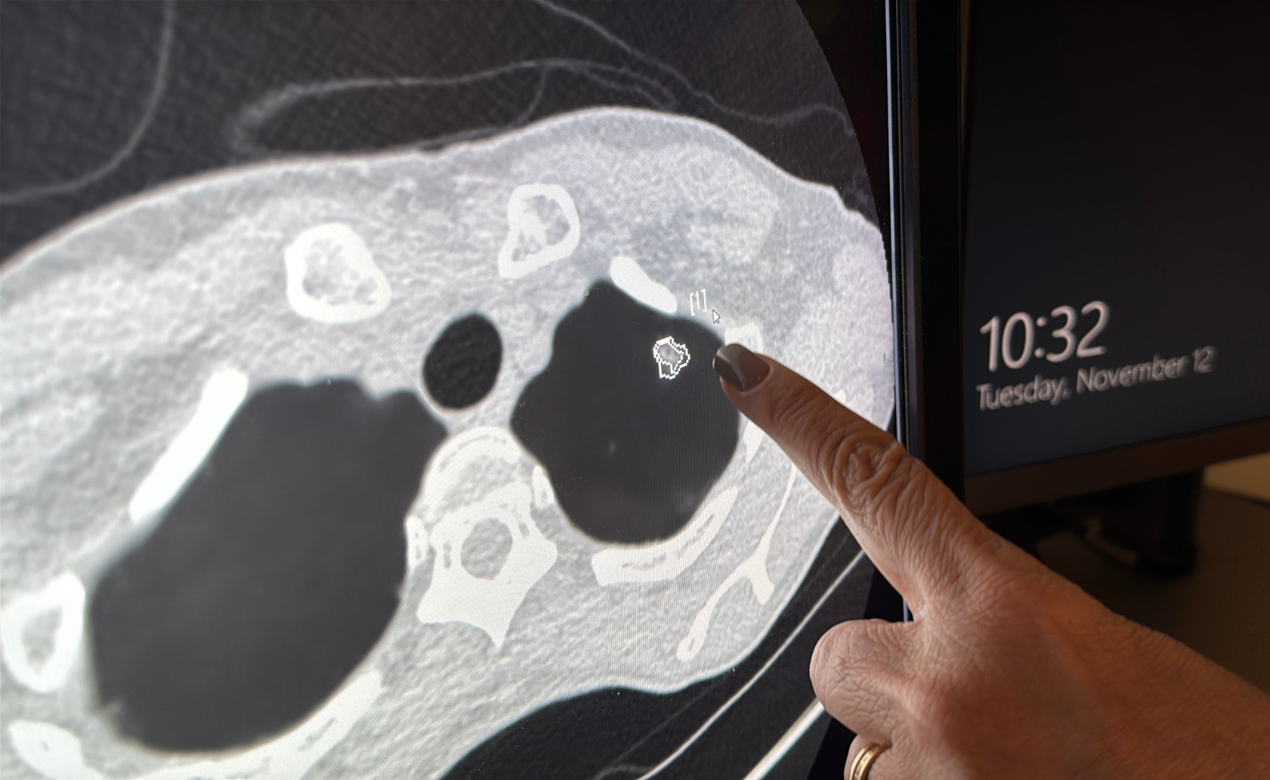

Bên cạnh sàng lọc và phân bổ hệ thống, bác sĩ Diệp Bảo Tuấn cho rằng công nghệ, đặc biệt là trí tuệ nhân tạo (AI) được nhấn mạnh như một hướng đi đột phá. Bác sĩ Tuấn chia sẻ AI được ứng dụng để hỗ trợ lập kế hoạch xạ trị, xạ trị thích ứng, hỗ trợ phẫu thuật nội soi, cho đến phân tích xét nghiệm phân tử để cá thể hóa phác đồ điều trị.